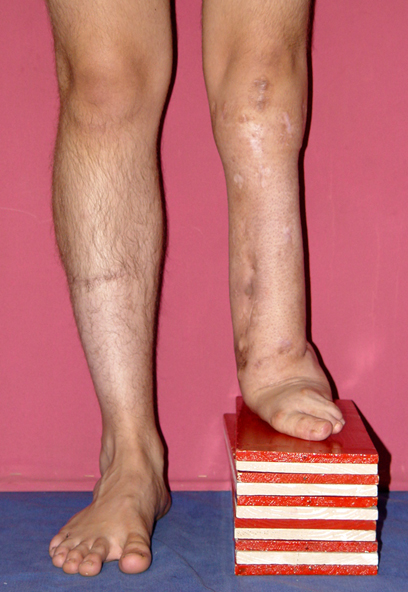

3. POSTTRAUMATIC LOWER LIMB SHORTNESS (MALUNION)

This type of shortness occurs after a fracture heals in a shortened position. Most cases are seen in adults and can be treated with one lengthening operation. Additional deformities can be corrected simultaneously. Most of these cases can be treated with lengthening over nail or just corrections and intramedullary nailing.